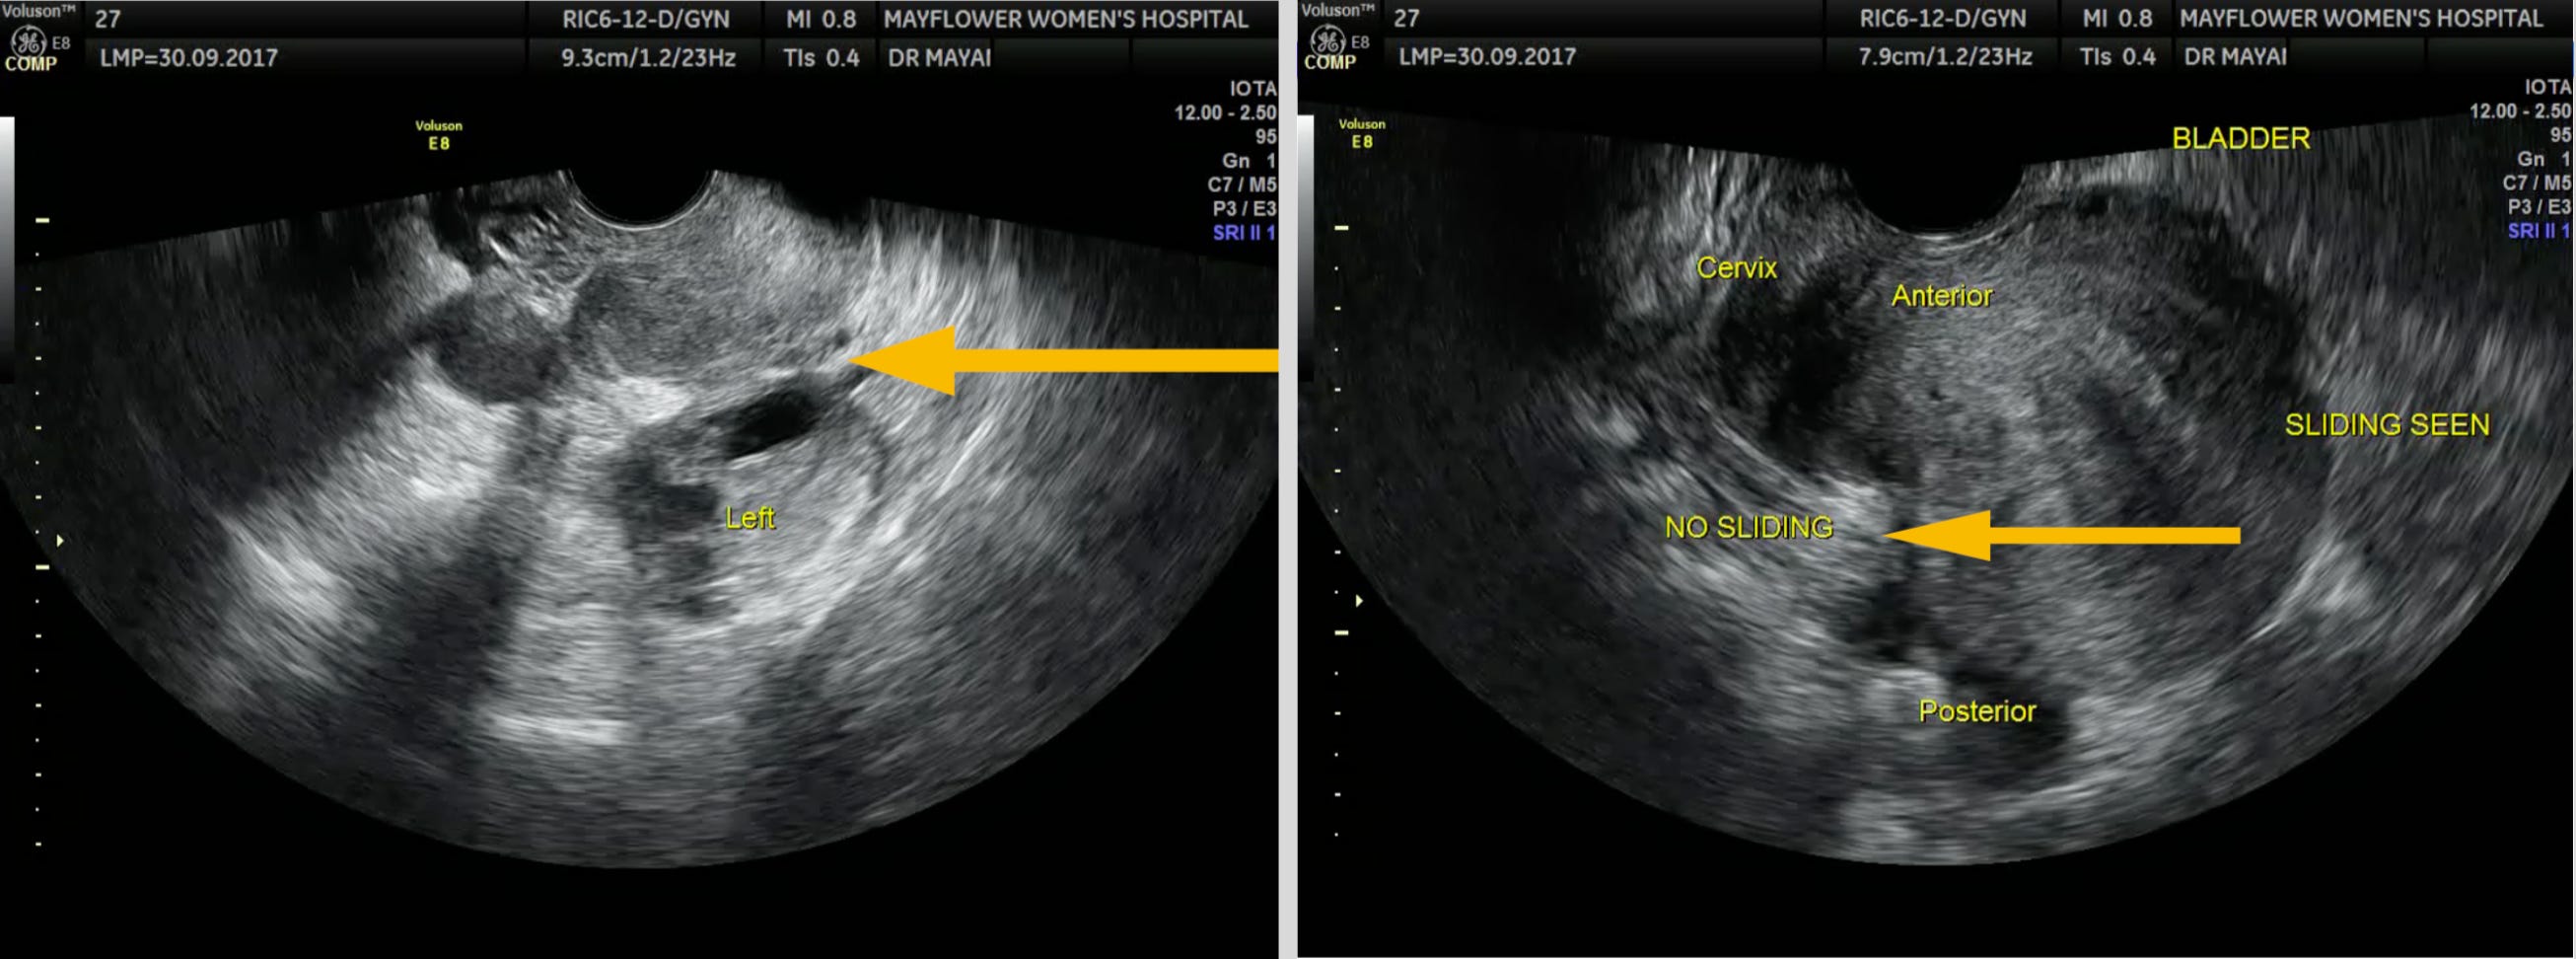

USG’s biggest benefit is availability. It’s a point of care instrument and owing to its wide range of applications, every gynae has one. Its second biggest benefit is live imagery.

Being able to move the TVS probe to observe sliding between the organs, might be the single most distinctive feature of the technology aiding in an early detection of adhesions inside the pelvis.

But USG can only go so far in determining the true extent of the disease. While it denotes the presence of endometriosis, it doesn’t help us accurately map the most damning feature of the disease. It’s infiltration.